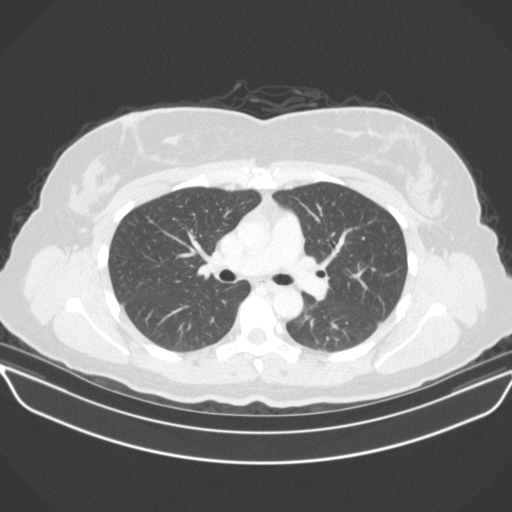

Targeted Slice 70 - HU-Space Analysis (Generated vs Real Venous)

0.885

HU SSIM

91.8

HU RMSE

40.2

HU MAE

Average HU-Space Metrics Across All Slices (38 slices) - Generated vs Real Venous

0.887

HU SSIM (Avg)

96.6

HU RMSE (Avg)

40.7

HU MAE (Avg)

Generated VENOUS CT scan (A→B translation)

No window - Raw intensity values

Lung window (WL -600, WW 1500 β†’ Low βˆ’1350, High +150)